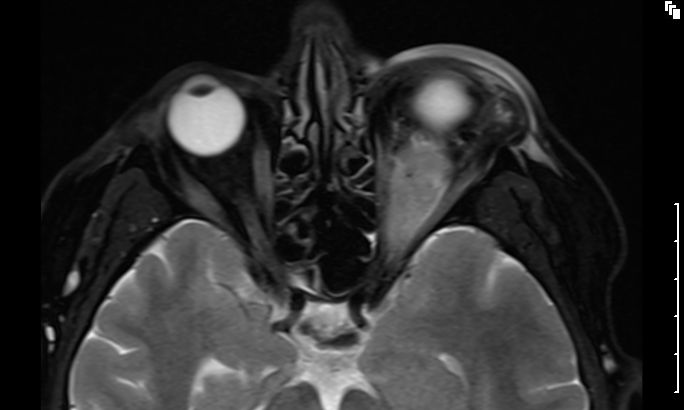

MRT eines retroorbitalen Lymphoms |